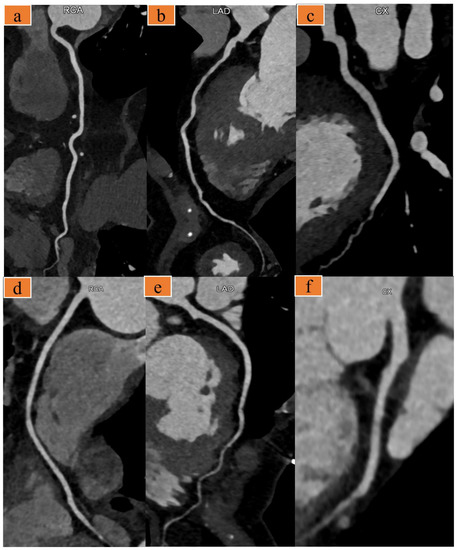

2.3. Image Reconstruction and Evaluation